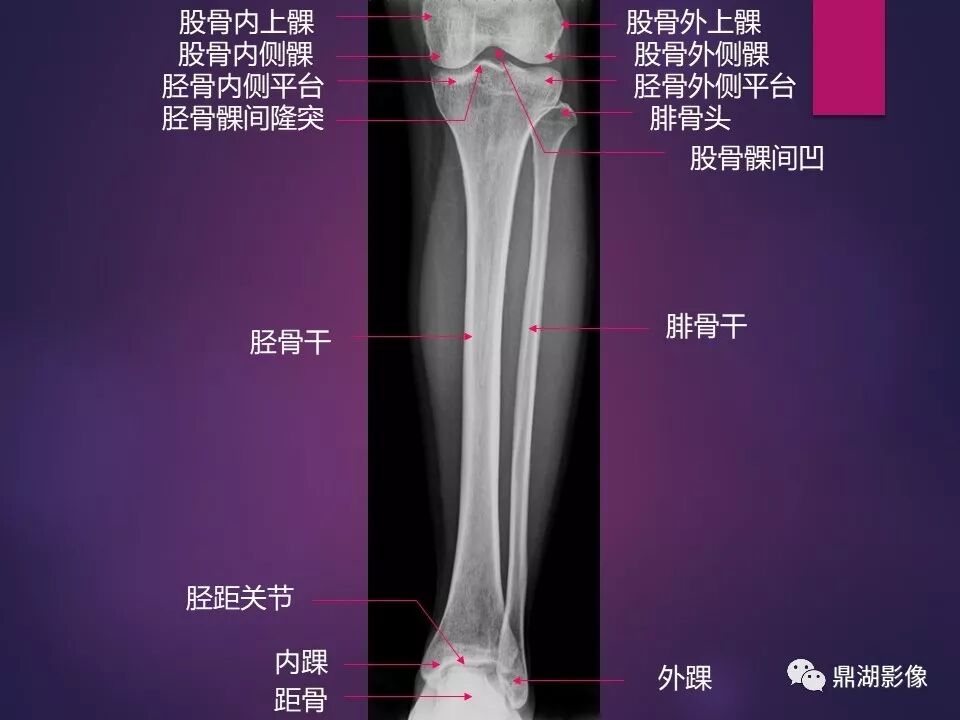

来源于:鼎湖影像 贵阳医学院医学影像系